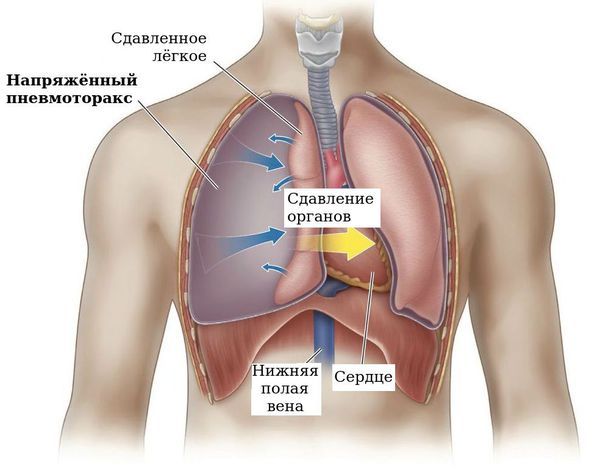

Схемы дыхания: Пневмоторакс на изображениях